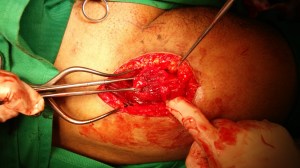

Surgical repair of his torn proximal rectus femoris was performed at 10 weeks post-injury.

The direct head was explored via an anterior surgical approach (Smith-Peterson). The rectus tendon was found to be completely torn from the anteiror inferior iliac spine (AIIS).

The torn muscle was identified and mobilised.

Suture anchor is applied to the anterior inferior iliac spine: